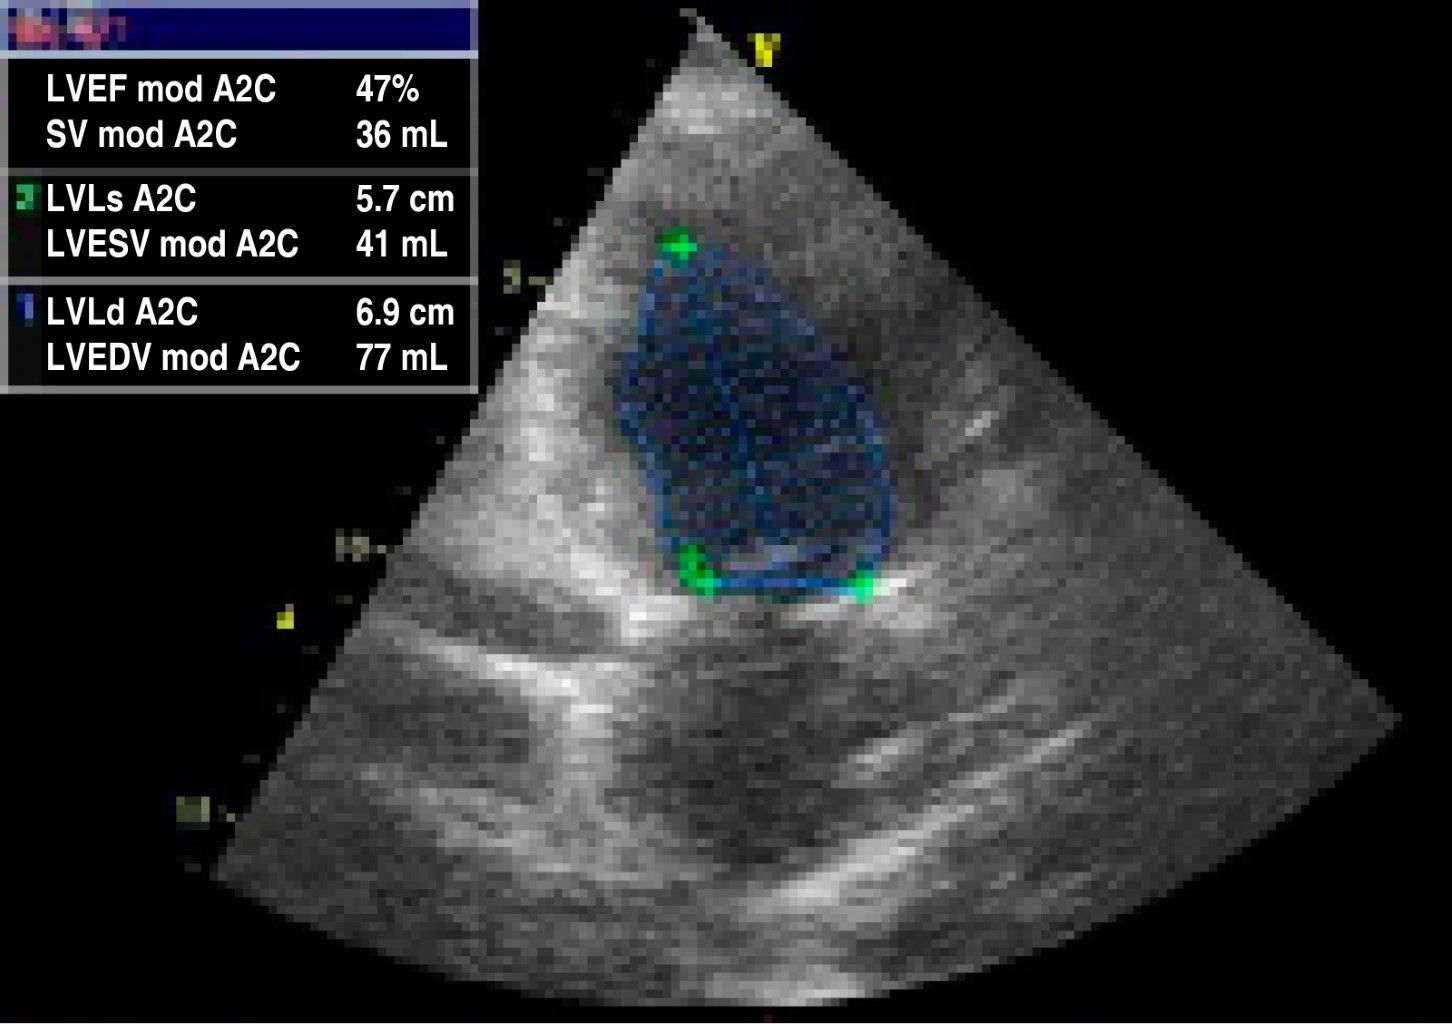

Figura 3